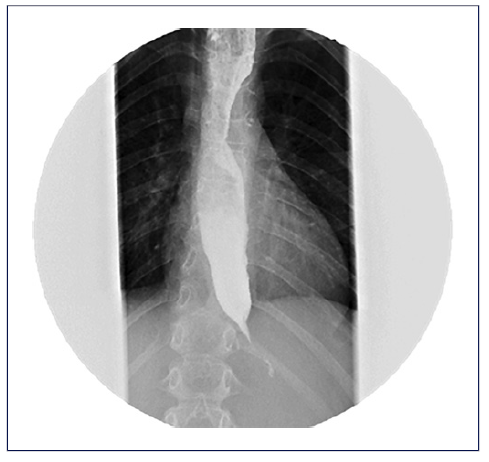

After an upper endoscopy with biopsies which revealed no significant endoscopic or histologic findings, an esophageal X-ray with contrast showed a persistently narrowed region at the end of the esophagus with a dilated esophagus above the narrowed region (Fig. 1). Hereafter, high-resolution manometry revealed type II achalasia, characterized by residual LES relaxation with an integrated relaxation pressure of 55.0 mm Hg (normal: less than 15.0 mm Hg) and 100% of failed swallows with 80% of panesophageal pressurization (Fig. 2).

Fig. 1 Esophageal X-ray with contrast showing a persistently narrowed region at the end of the esophagus with a dilated esophagus above the narrowed region.